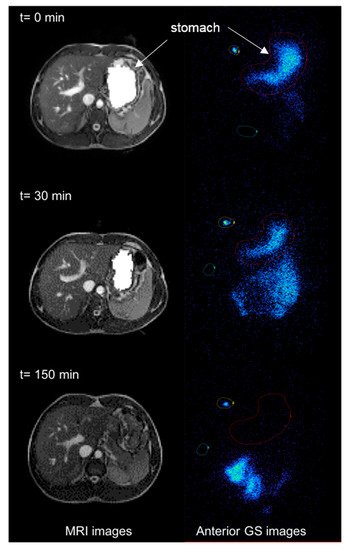

3.1. MRI

3.2. GS